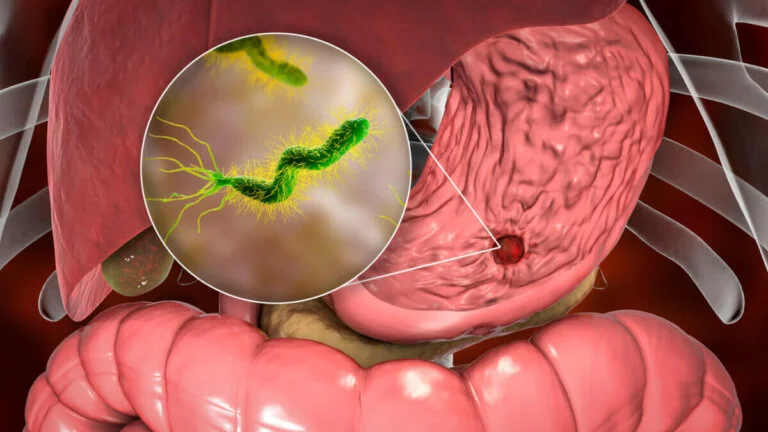

El tratamiento del sistema inmunológico está orientado a fortalecer las defensas naturales del cuerpo, ayudando a prevenir infecciones y a mejorar la capacidad del organismo para responder de manera adecuada ante bacterias, virus y otros agentes externos.

Este tratamiento puede incluir una combinación de evaluación médica, suplementación específica, recomendaciones nutricionales y cambios en el estilo de vida, siempre de acuerdo con las necesidades de cada paciente.